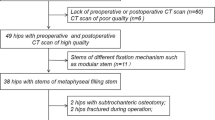

We reviewed preoperative radiographs from 50 of 67 patients (79 hips) who had a primary diagnosis of DDH and underwent primary THA from January 1999 to February 2007 inclusive. Hips with prior femoral-sided surgery (n = 2) or without preoperative films (n = 19) were excluded. Furthermore, patients with bilateral hips had the second hip excluded (n = 8). Twenty-one of 50 received a modular femoral stem based on the criterion of intraoperative neck-shaft anteversion of greater than 25° as measured by the senior surgeon (CLP), whereas the remainder received tapered nonmodular stems. There were no differences in age, sex, height, or weight between the modular stem group and tapered stem group. Radiographs were evaluated to record the parameters listed.

After we received an exemption from the institutional review board for secondary data analysis, we performed a retrospective search of our surgical database. We identified 630 primary THAs that were performed by the senior author (CLP) between February 1999 and January 2007 inclusive. From these, we identified 79 hips in 67 patients who had a primary diagnosis of DDH as determined by lateral center-edge angle < 20° and an upwardly sloping acetabular sourcil. Hips were excluded if they had a history of prior femoral-sided hip surgery (n = 2) or did not have digital preoperative films available (n = 19). This resulted in a series of 58 hips in 50 patients. To avoid potential bias related to bilateral hips and implant selection, where the surgeon might use a modular stem in the second hip because it was used in the first, the first hip that underwent THA was selected for the review resulting in 50 patients with 50 hips. We assessed operative reports to identify the type of implant used and the rationale for the implant. S-ROM modular femoral stems (DePuy Synthes, Warsaw, IN, USA) were placed in 21 of 50; the remaining 29 patients received a tapered nonmodular stem (Biomet Orthopaedics, Warsaw, IN, USA). This stem has a moderate metaphyseal flare that does not accommodate excessive anteversion (Fig. 1). In this single-surgeon experience, the rationale for femoral stem selection was principally based on femoral anteversion: if femoral anteversion was estimated to be greater than 25° by the senior surgeon during surgery, a modular stem was typically selected. There were no differences in patient age, height, weight, or sex between the modular stem (MS) group and tapered stem (TS) group (Table 1).